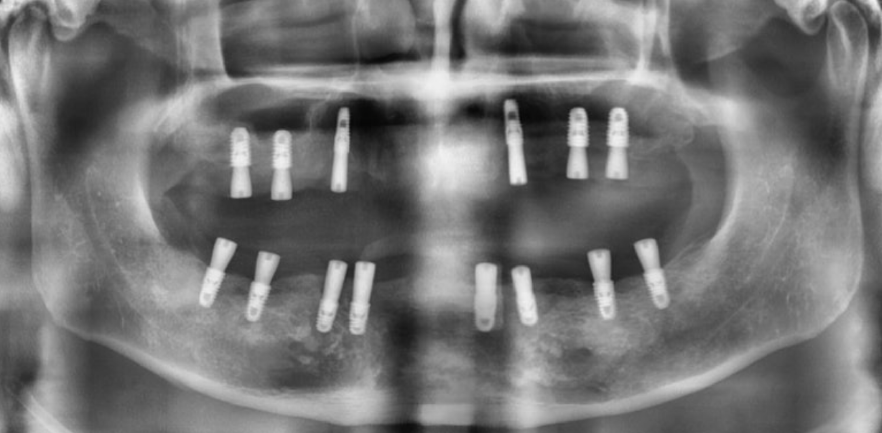

나이가 들면서 전체 치아가 흔들리거나 손상되어 발치 후 전체 임플란트(전악 임플란트)가 필요한 경우가 많아요. 특히 만 65세 이상 환자분들은 평생 1인당 2개까지 임플란트 건강보험 혜택이 적용되니 꼭 확인해 보세요! 이번 증례는 심각한 잇몸 질환으로 모든 치아를 상실한 60대 환자분께서 정교한 맞춤형 전악 임플란트를 통해 건 강한 미소와 저작 기능을 회복한 과정입니다. CASE. 60대 남성 환자, '전체 치아 흔들림'으로 내원 "전체 치아가 흔들리고 아파서 임플란트를 하고 싶어요." 여러 치과를 알아보시던 중, 지인의 소개로 저희 병원을 찾아주셨습니다. 처음부터 전악 임플란트를 염두에 두고, 풍부한 임상 경험을 가진 의료진을 찾고 계셨습니다. 정밀 진단 결과 구강 검진 및 CT 촬영 결과, 환자분의 상태는 매우 심각했습니다. * 구강 상태: 위아래 모든 치아가 심하게 흔들리고, 치아 뿌리가 노출될 정도로 잇몸 조직이 붕괴된 상태였습니다. * CT 및 파노라마 소견: 치아를 지지해야 할 잇몸뼈(치조골)가 염증으로 인해 대부분 소실되어, 치아들이 뼈 속에서 떠 있는 '부유치(floating tooth)' 상태였습니다. 자연치아를 최대한 보존하는 것이 원칙이지만, 이미 치아 뿌리 끝까지 염증이 퍼져 회복이 불가능했습니다. 환자분께 상태를 자세히 설명드린 후, 전체 발치 및 전악 임플란트 계획을 수립했습니다. ![]() ![]() 개인별 맞춤 치료 계획 환자분의 구강 구조와 심미성을 고려하여 아래와 같이 맞춤형 치료 계획을 세웠습니다. * 상악 (윗니): 6개의 임플란트 식립 후 '임플란트 지지 부분틀니 (IARPD)' 붕괴된 앞니 잇몸과 입술의 볼륨감을 심미적으로 회복시키기 위해, 어금니는 임플란트 고정성 보철로 단단히 잡아주고 앞니는 틀니의 잇몸 부분(flange)을 이용해 자연스러운 외모를 재현하는 방식입니다. * 하악 (아랫니): 8개의 임플란트 식립 후 전체 ‘고정성 보철' 전체 치아를 임플란트와 보철물로 단단하게 고정하여 본래 치아처럼 편안하게 사용하는 방식입니다. 치료 과정 1. 발치 및 잇몸 회복 모든 치아를 발치한 후, 염증이 완전히 사라지고 잇몸이 안정될 때까지 약 2개월간 기다렸습니다. 이 기간 동안 환자분의 식사와 심미성을 위해 임시 틀니를 제작해 드렸습니다. ![]() 2. 정확하고 안전한 임플란트 식립 - 상악수술: 잇몸뼈가 얇아 고난도 수술인 상악동 거상술을 동반하여, 계획된 위치에 정확하게 6개의 임플란트를 식립했습니다. 충분한 마취와 정교한 수술, 그리고 숙련된 봉합으로 환자분의 불편감을 최소화하고 빠른 회복을 유도했습니다. ![]() - 하악수술: 최종 보철물의 형태와 기능을 고려하여 적절한 간격과 위치에 8개의 임플란트를 완벽하게 식립했습니다. ![]() 3. 뼈 유착 및 2차 수술 임플란트가 뼈와 단단히 붙는 약 3~4개월 동안 임시 틀니를 사용하며 기다립니다. 이후 모든 임플란트의 ISQ 수치(임플란트 안정성 지수)가 양호한 것을 확인하고, 잇몸 밖으로 임플란트를 노출시키는 간단한 2차 수술을 진행했습니다. ![]() 4. 임시 보철 및 최종 보철 준비 현재는 최종 보철물을 올리기 전, 임시 보철물(PMMA)을 사용하여 환자분이 적응하는 단계를 거치고 있습니다. 임플란트가 완벽하게 식립되었기 때문에 성공적인 최종 결과가 기대됩니다. 전악 임플란트는 단순한 치아 보철을 넘어, 무너진 식생활과 자신감을 회복하는 중요한 치료입니다. 이백점치과는 최소한의 임플란트 식립으로 통증과 불편을 줄이면서도 안정적이고 심미적인 결과를 추구합니다. 풍부한 임상 경험과 높은 환자 만족도로 증명된 실력으로, 치아가 전혀 없는 분들도 다시 편안한 식사와 활짝 웃는삶을 되찾을 수 있습니다. 당신의 현명한 선택, 이백점치과와 함께하세요. |